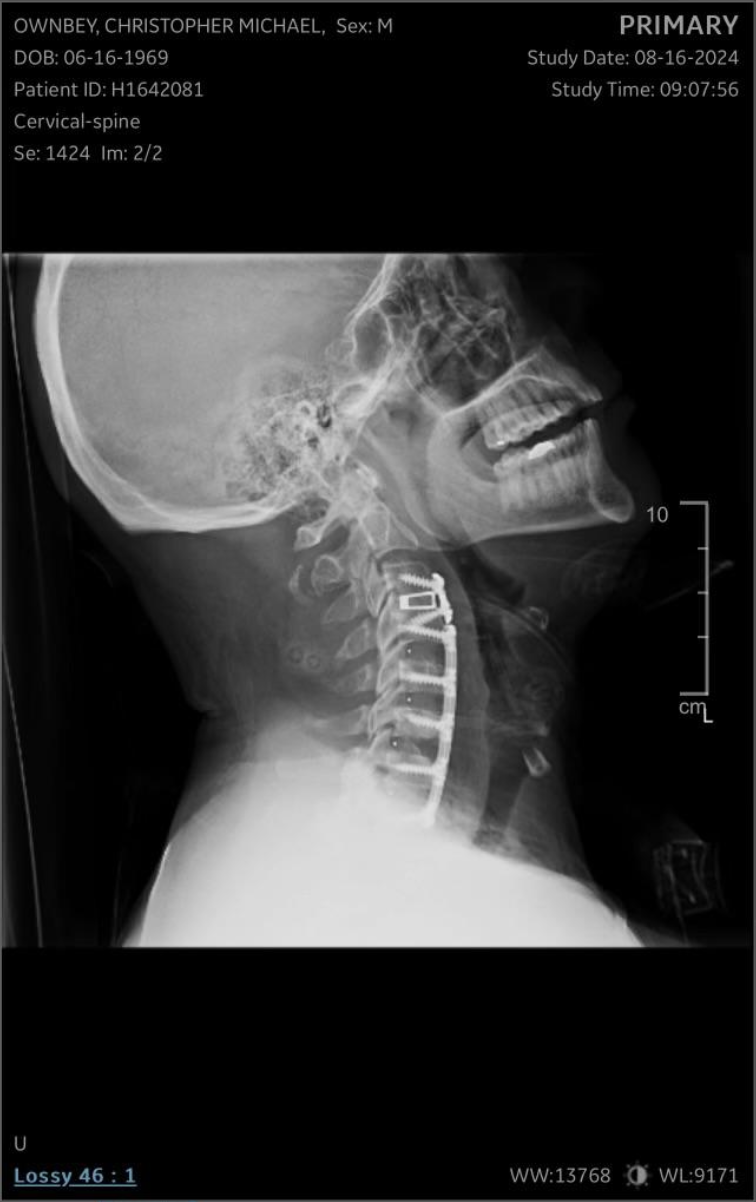

He’s fought through multiple back and neck surgeries, battled setbacks that would’ve stopped most people, and carried the responsibility of raising two boys 24 years apart, with two grandchildren depending on his example. Slowing down was never an option.

2024 was his year of full neck and back fusion — and his comeback.